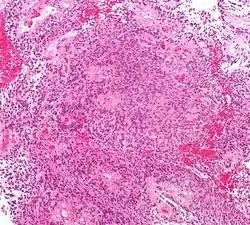

- Основным гистологическим типом является истинная эпендимома , для которой типично наличие периваскулярных и истинных «розеток». Периваскулярные «розетки» («псевдорозетки», «лучистая корона») состоят из клеток новообразования, которые располагаются вокруг кровеносных сосудов. В истинных «розетках» опухолевые клетки находятся вокруг каналов, которые выстланы эпендимарными клетками.